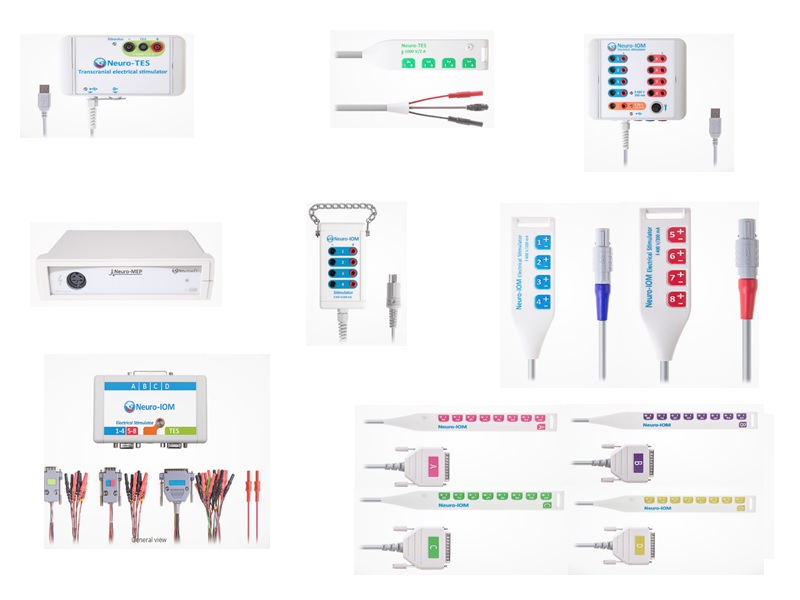

- IOMN - Neuromonitorização Intraoperatória Neurofisiológica

- Acessórios equipamento IOM